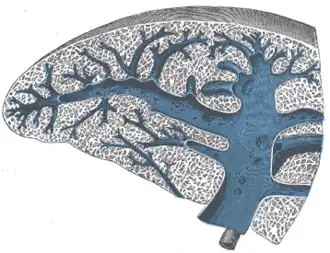

Transverse section of the spleen, showing the trabecular tissue, the splenic vein and its tributaries. | |

The smaller veins unite to form larger veins that do not accompany the arteries, but soon enter the trabecular sheaths of the capsule, and by their junction form six or more branches, which emerge from the splenic hilum, and, uniting, constitute the splenic vein, the largest radicle of the portal vein.